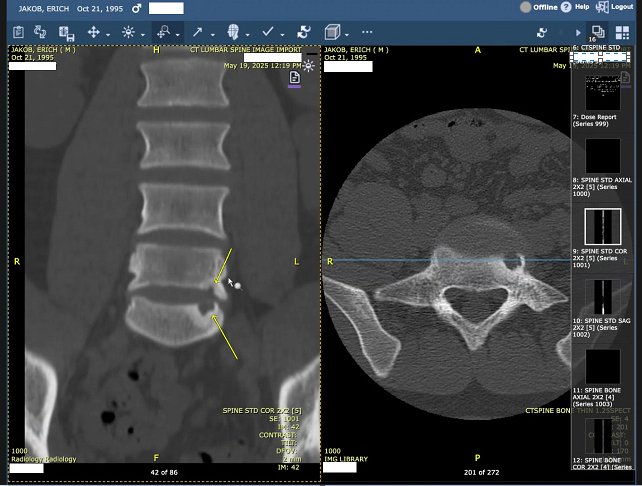

Erich is 29 and has been living with constant, debilitating pain from severe spinal damage. His condition has progressed so much that he can’t sit upright, struggles to sleep, and is mostly confined to bed. It’s been heartbreaking to watch someone I love lose access to the simple things that make life feel normal. Going outside, seeing friends, even standing long enough to cook a meal all have become excruciating.

Over the past several months, Erich has already spent thousands of dollars out of pocket on physical therapy, nerve studies, epidural injections, medications, and consultations with specialists. Despite following every conservative treatment step doctors recommended, his insurance has continued to deny the one procedure multiple spine surgeons agree could provide meaningful relief: artificial disc replacement surgery. These denials don’t reflect the reality of his condition or his treatment history. With every month that passes, his pain worsens and his need for surgery grows more urgent.